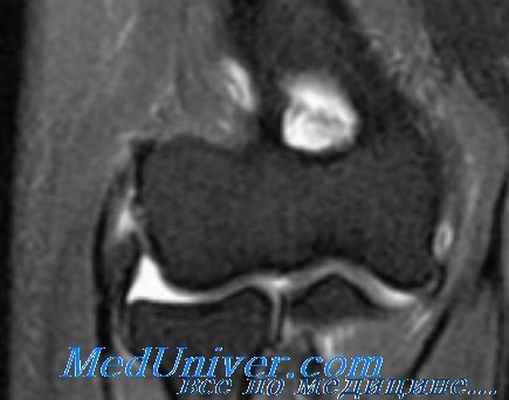

- МРТ и биохимический анализ крови проводятся, когда необходимо дифференцировать эпикондилит с другими заболеваниями или травмами (перелом, туннельный синдром или СГС).

Для точности диагноза врач может назначить дополнительные исследования: УЗИ локтевого сустава, рентген для четкого изображения плотных структур, магнитно-резонансную томографию (МРТ) для изображения мягких тканей тела, включая мышцы и сухожилии. Если ваш врач считает, что симптомы могут быть связаны с проблемой шеи, может назначаться МРТ шеи, чтобы узнать, есть ли у вас грыжа межпозвоночного диска или артритические изменения. Оба эти состояния могут вызвать боль в руке.